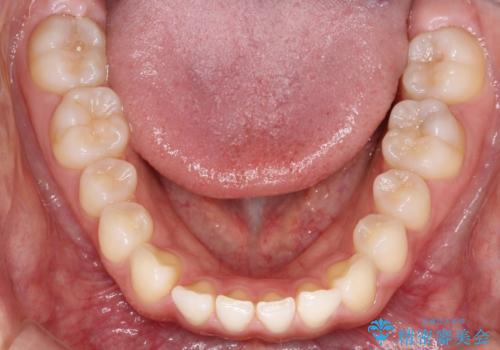

すきっ歯のインビザラインによる目立たない矯正

- すきっ歯を治したいとのことで来院されました。

上下ともに前歯に隙間がありました。

目立たない装置をご希望のためインビザラインで矯正治療を行うこととしました。

使用時間を守っていただけたので、スムーズに治療を終わることができました。